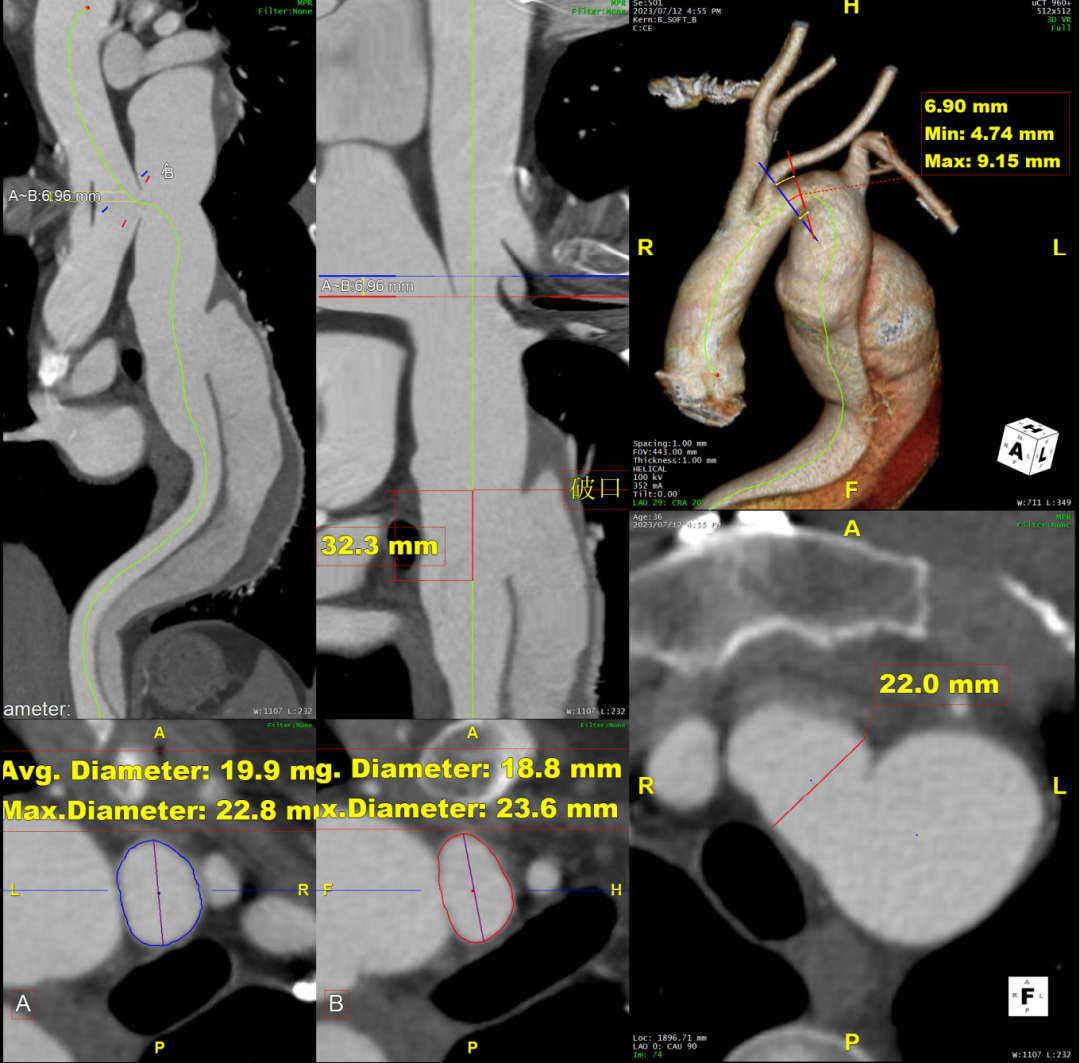

术前CTA评估与测量

术前CTA提示主动脉夹层(Stanford B型,Debake llI型),主动脉弓及降主动脉瘤样扩张,累及左锁骨下动脉起始段,管径最粗约7.4cm,夹层初破口位于降主动脉起始段,向下累及至腹主动脉(约平胸12椎体水平),真腔小,假腔大,腹腔干发自混合腔,肠系膜上动脉、下动脉,双肾动脉均起自真腔,双肾灌注未见差异。

术前三维重建

术前CTA详解:

病例特点

1. 弓型陡峭,成角;

2. 自左颈总后缘小弯侧锚定区不足1cm;

3. 巨大破口,约33mm,病变累及至腹腔干平面。